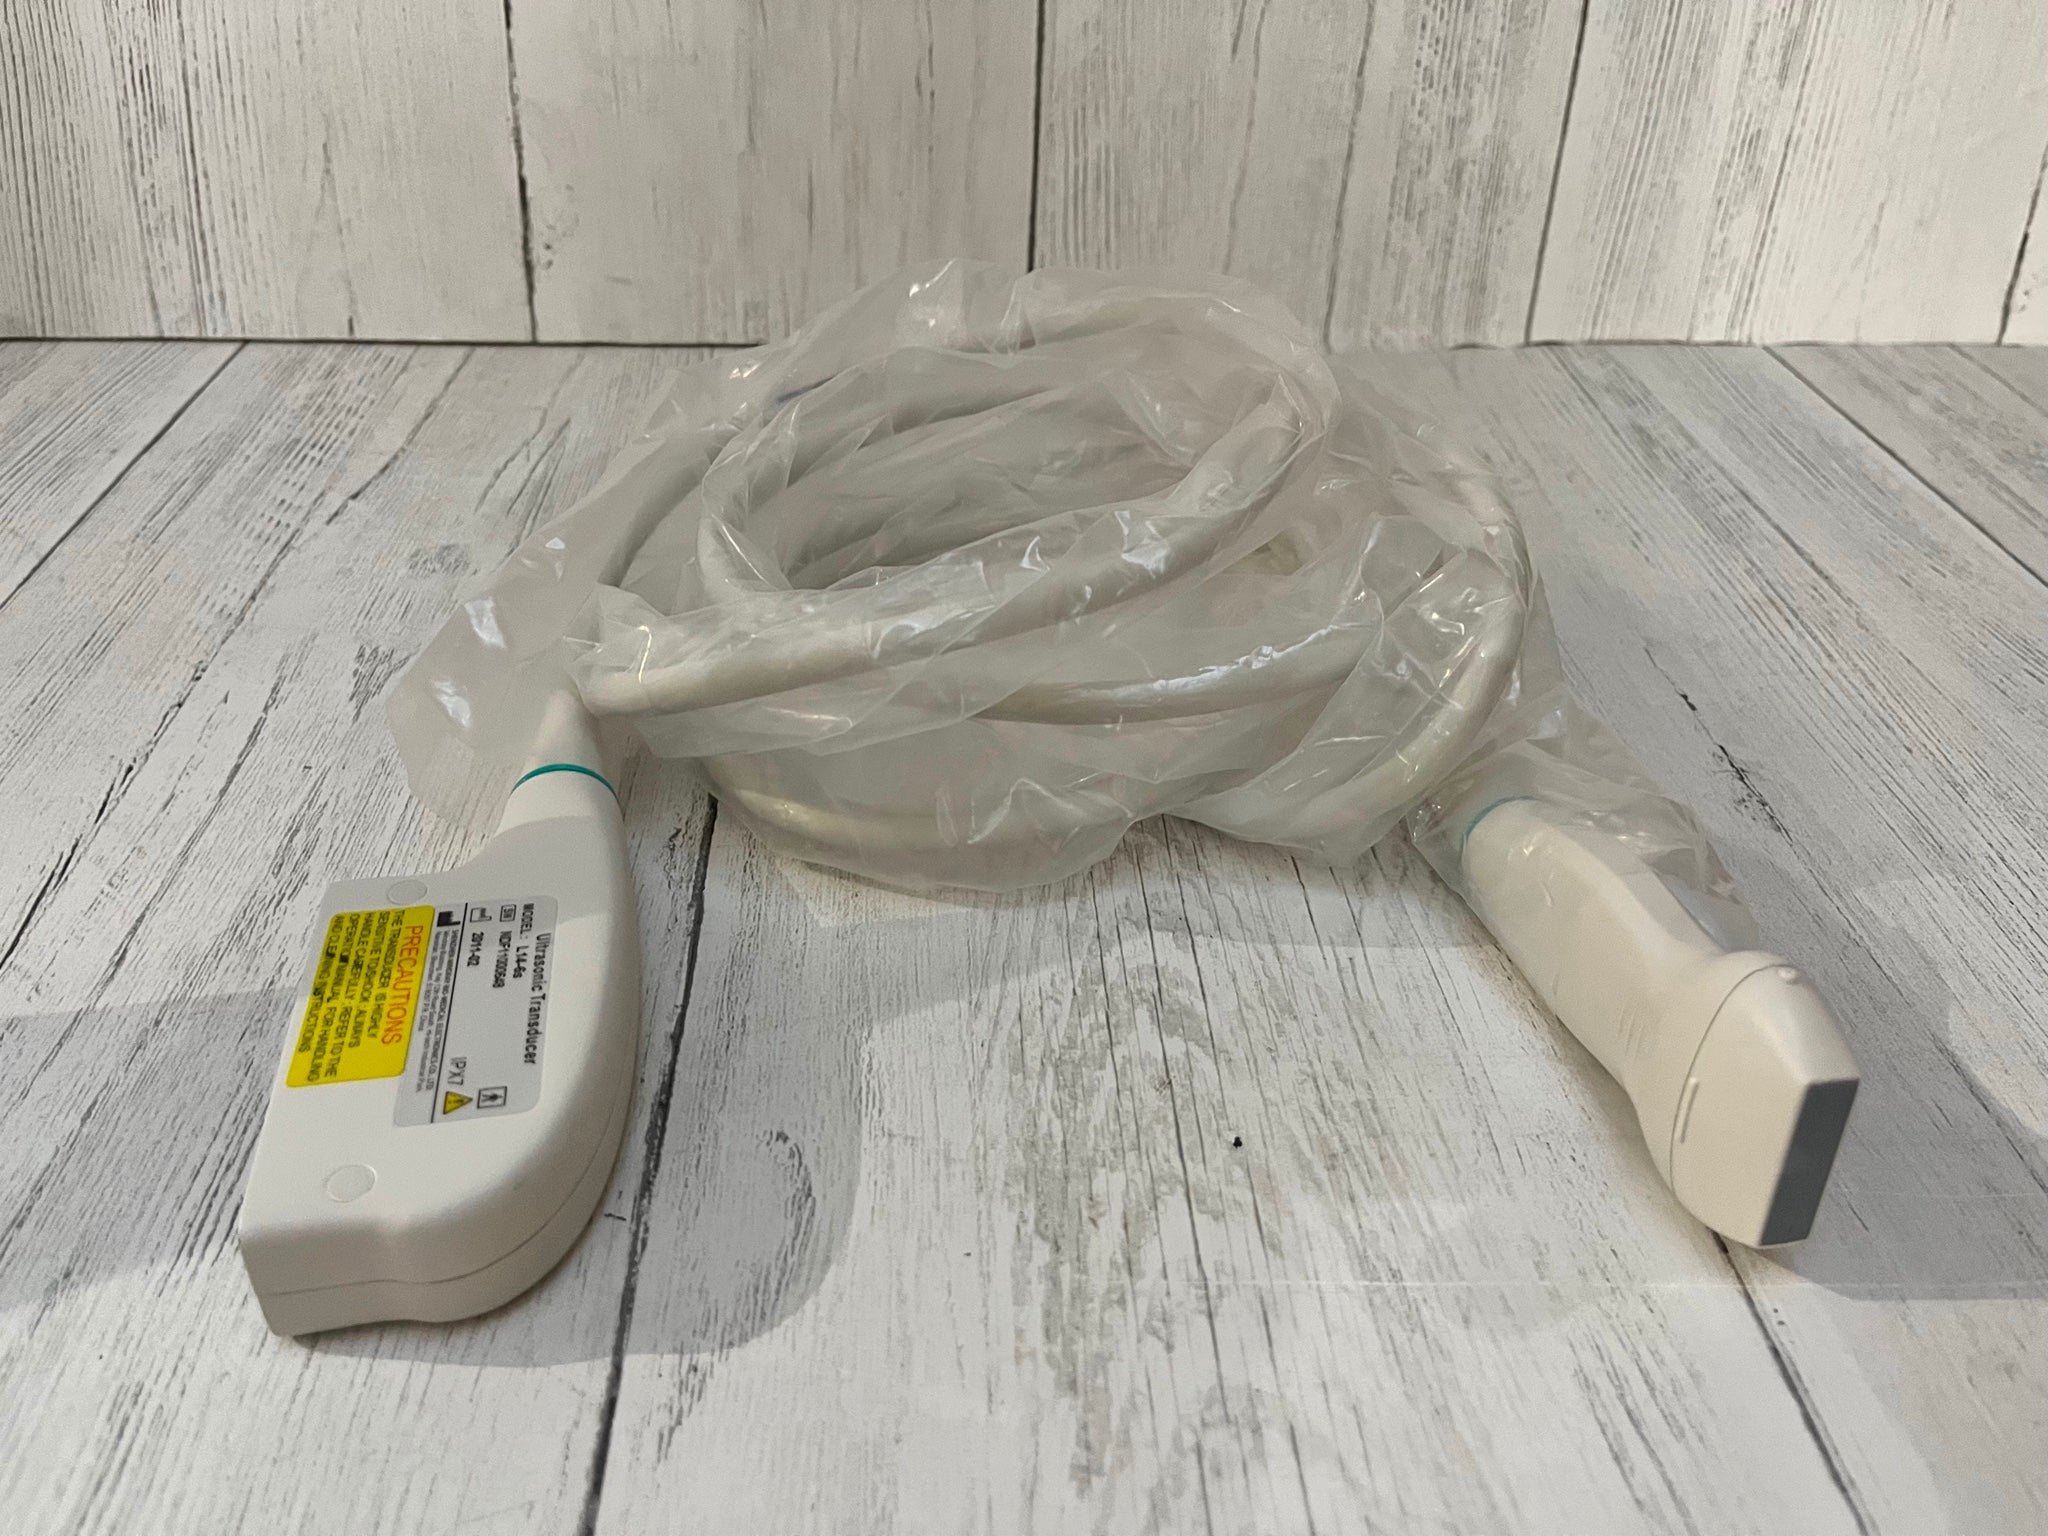

This state-of-the-art machine comes with two probes, ensuring versatility for different diagnostic needs. The SIUI Apogee 2300 supports DICOM (Digital Imaging and Communications in Medicine) which allows seamless integration with hospital information systems and ensures efficient workflow and storage management. The portability of this machine does not compromise its performance, as it delivers crystal-clear images that are critical for precise diagnostics.

In addition to its technical features, the Portable OB/GYN Ultrasound Machine is also designed with patient comfort in mind. The smooth operation and efficient scanning reduce the need for lengthy or repeated procedures, minimizing discomfort and improving patient experience. The two included probes offer flexibility in imaging, allowing for both abdominal and transvaginal examinations with ease.